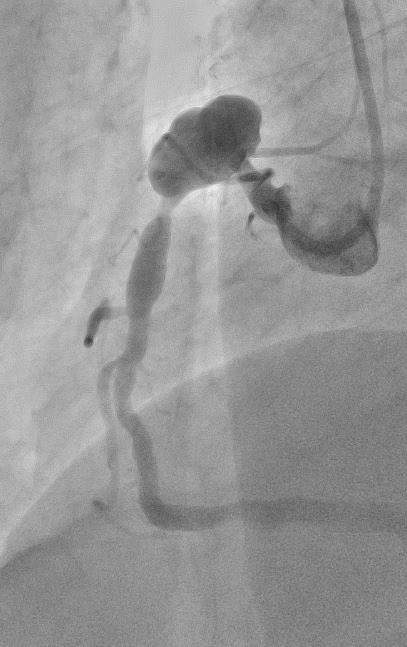

CTA and invasive angio: open IMA graft to LAD and vein graft to RCA, in-stent occlusion of vein graft to ramus intermedius. CT done in preparation for CTO recanalization of ramus. #cardiotwitter @escardio @mirvatalasnag @Drroxmehran @M_Marwan_ @M_Ijgua @HolgerNef @UniFAU

3

28

96